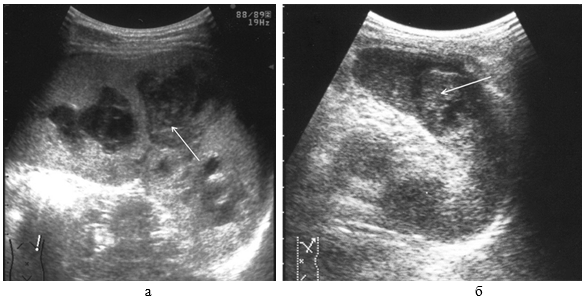

Ушибы селезенки сопровождаются интерстициальным отеком и геморрагическим пропитыванием тканей. Прямыми эхографическими признаками в первые 3–5 часов после травмы являются снижение эхогенности паренхимы и четкости контура органа, а также «разреженность» эхоструктуры паренхимы. Геморрагическое пропитывание паренхимы манифестировало наличием гиперэхогенных зон с нечеткими размытыми контурами в области повреждения (рис. 1). Характерно увеличение размеров всей селезенки или преимущественно поврежденного сегмента с нарушением ее конфигурации. Результаты цветового допплеровского картирования свидетельствуют о снижении кровотока, степень которого коррелирует с выраженностью эхографических проявлений отека паренхимы.

Рис. 1. Ушиб селезенки. Зона геморрагического пропитывания указана стрелками.

В динамике острого периода травмы, в течение 2–3-х суток, отмечается тенденция к уменьшению размеров органа (сегмента) и восстановлению его конфигурации, к нормализации эхогенности паренхимы с одновременным снижением эффекта «разреженности», к повышению четкости контура.

Указанные изменения обусловлены инволюцией отека тканей, завершавшейся к 5–7-м суткам посттравматического периода. В то же время постепенное исчезновение гиперэхогенных зон без четких контуров прослеживается на протяжении 2–3-х недель, что свидетельствует о редукции геморрагического пропитывания паренхимы.